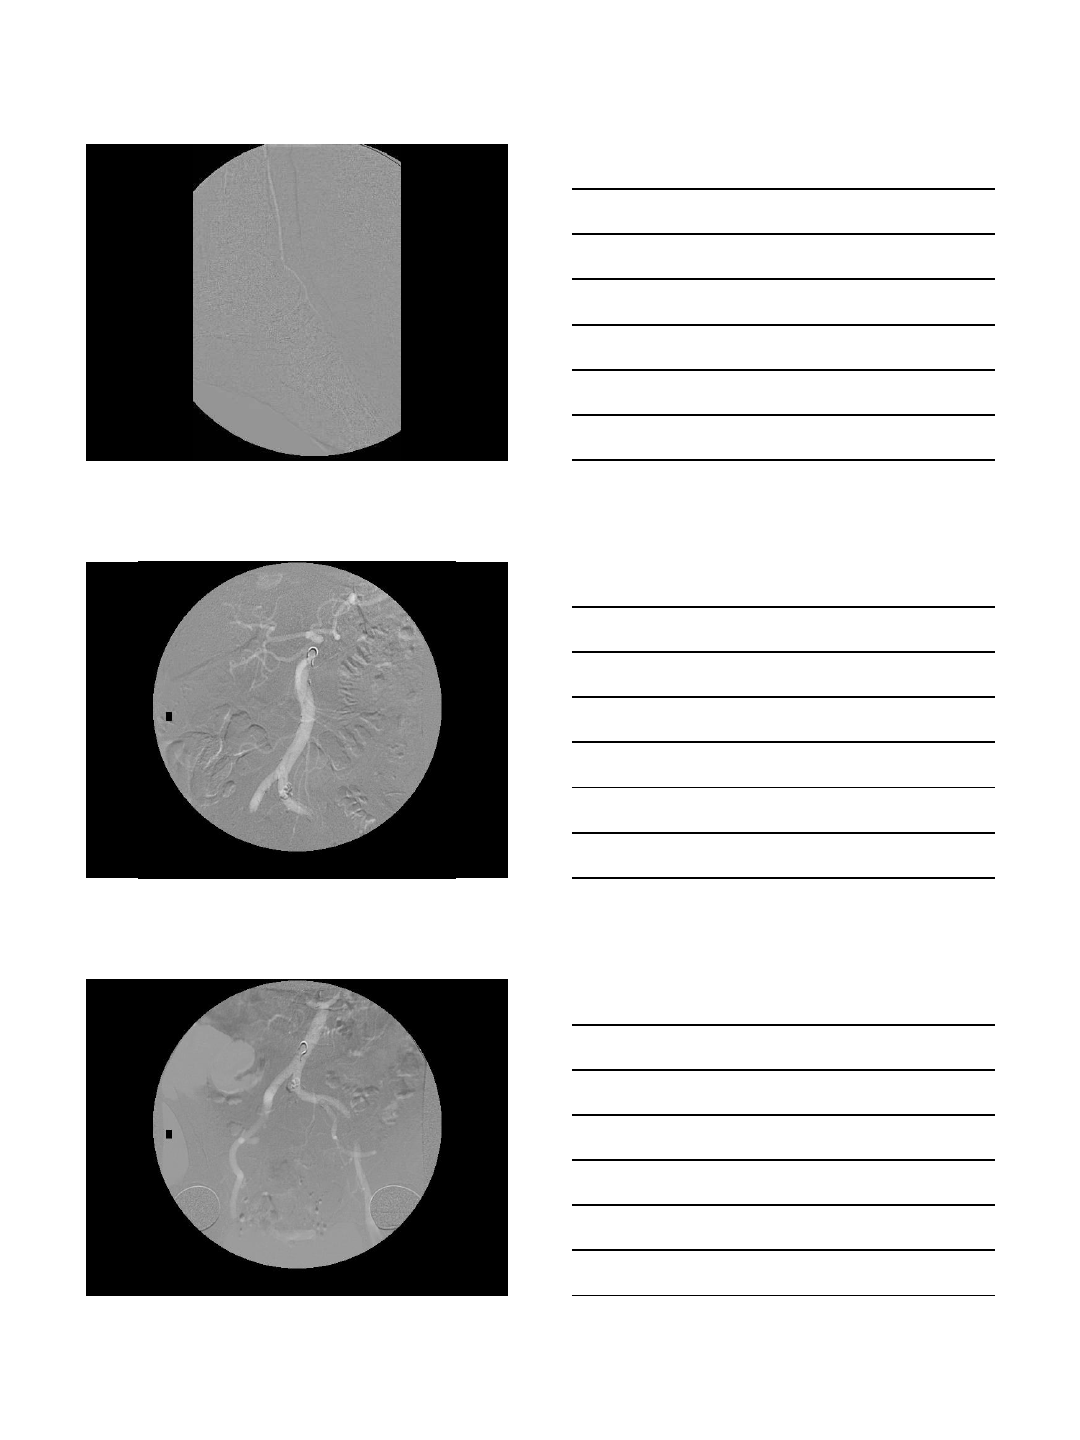

Carbon Dioxide Imaging

Subtracted Image Aorta filled with CO2 -

unsubtracted image

Carbon Dioxide Imaging with

Interventions